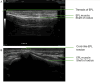

Spontaneous rupture of the extensor pollicis longus (EPL) tendon has been reported to be uncommon. Several possible causes and precipitating factors have been reported for this rupture, including prior surgery to the distal radius. We report the case of an 18-year-old male professional athlete who presented with an inability to extend their left thumb. They presented with this condition after open reduction and internal fixation (ORIF) for a fractured left distal radius. Findings were consistent with the rupture of the EPL tendon. The typical presentation of such a rupture is one to four months after ORIF surgery, a shorter delay than seen in the present case, which exceeds one year. They underwent surgical tendon transfer using the extensor indicis tendon, and a dorsally protruding surgical screw was removed from the volar aspect of the radius. In this case, we suggest that repetitive friction from the protruding surgical screw, following volar plating of a distal radius fracture, may have caused abrasion of the EPL tendon. This may have predisposed it to rupture. This can occur long after the placement of a volar plate and must be considered as a potential cause of an EPL tendon rupture.